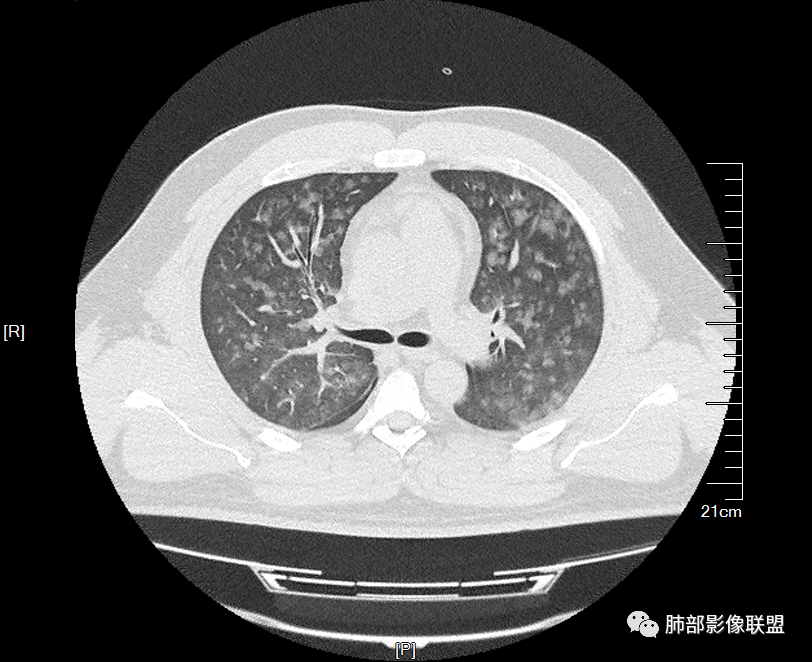

双肺多发弥漫性磨玻璃结节影,大小不一,形态不规则,部分融合,支气管未见明显扩张,部分血管束略增粗,叶裂胸膜增厚,临床有痛风,左足痛6天,考虑:1:痛风结节(一般实性结节,很少磨玻璃结节影)2:血管炎?3:病毒性肺炎(水痘-疱疹肺炎?)

双肺多发腺泡结节及磨玻璃,小叶间隔增厚(大网格状),腺泡结节内及磨玻璃内可见细网格影(小叶内间隔增厚),影像表现符合肺泡出血改变,血肌酐升高,考虑肺肾综合征。鉴别肺水肿。

年轻男性,痛风史,高血压史,肌酐高,左足痛6天入院。胸CT:双肺多发弥漫性磨玻璃结节影,大小不一,部分融合,上中下肺都有,中内带多,胸膜下少。部分血管束略增粗,小叶内间隔、小叶间隔增厚,下肺明显,左室大。叶裂胸膜增厚。临床有痛风,左足痛6天,考虑:心衰、间质性肺水肿?弥漫性肺泡出血?鉴别:MPA,肺肾综合征,痛风结节等。

多发GGO结节,边界清,以全小叶、小叶中心为主:

GGO背景

中轴间质稍增厚

中轴间质增厚,小叶间隔增厚,小叶内间质增厚,部分重力作用,双侧对称,胸水,按理淋巴道回流受阻有

1.间质性肺水肿 :小叶间隔增厚,尚光滑,支气管血管束增粗,胸膜或叶间裂增厚,肺内有磨玻璃密度影,有重力分布趋势。

2.肺泡性肺水肿 :

(1)中央型分布:以肺门为中心,两肺中内带对称分布的大片状实变,称为“蝶翼征”。常见于心源性及肾源性肺水肿患者。也可表现为磨玻璃密度病灶,弥漫性分布或以小叶中心性分布。

(2)弥漫型肺水肿:弥漫分布于两肺内的多发斑片状磨玻璃密度及实变影,大小和密度不等,可融合成大片状阴影,可见空气支气管征。